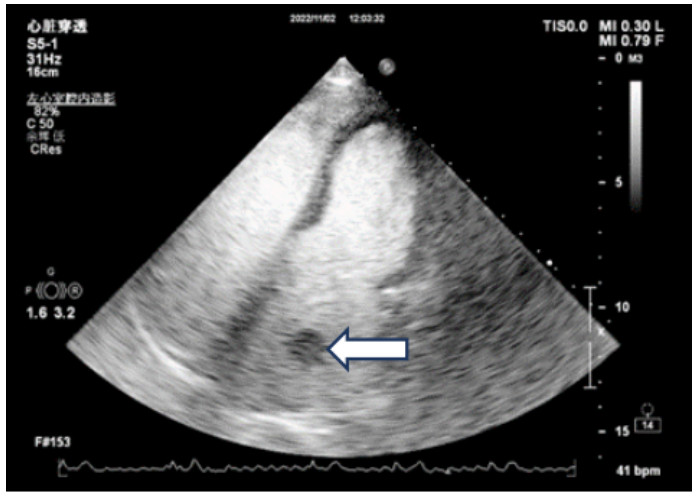

既往史:有高血压病史10年余,规律降压治疗,未监测血压。房颤病史2年余,2022年11月在本院超声心动图显示左心房见一不均质低回声团,位置随心动周期漂动(17 mm×16 mm)”(见图 1),左房前后径40 mm,左右径46 mm,上下径70 mm。LVEDD 39 mm,LVEF:60%。二尖瓣E峰0.92 m/s,最大压差3.39 mmHg(1 mmHg=0.133 kPa)。反流面积3.8 cm2,二尖瓣口频谱呈单峰。舒张期二尖瓣口前向血流,E < A,无舒张功能不全。进一步行经心脏超声造影提示:Flash后,左心室心腔内团块未见明显灌注(见图 2)。

| 注:Flash后,左心室心腔内团块影(箭头处)未见明显灌注 图 2 经患者肘静脉注射造影剂“声诺维”后行心脏超声造影(左心声学及心肌灌注) |